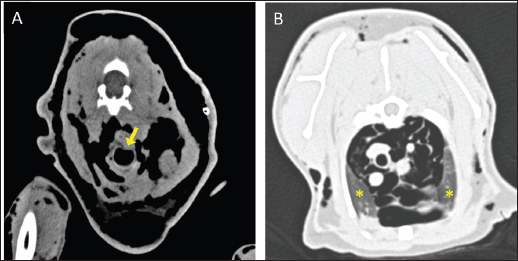

On arrival, venous blood gas analysis revealed mild respiratory acidosis and mild hyperlactatemia (Table 1). The complete blood count revealed moderate thrombocytopenia and neutrophilic leukocytosis (Table 2). Biochemical analysis showed elevated liver and muscular enzyme levels and increased serum amyloid A levels (Table 2). Hypofibrinogenemia (1.36 g/l) with unremarkable coagulation time was evident. All abnormalities were consistent with the traumatic event suspected. Thoracic radiographs confirmed the presence of severe subcutaneous emphysema, associated with moderate pneumomediastinum and mild pneumothorax (Fig. 1). Computed tomography (CT) was scheduled for the following day due to the high suspicion of tracheal injury associated with cervical compressive myelopathy. The cat was hospitalized at the intensive care unit under strict monitoring, minimizing manipulation as much as possible. Fluid therapy was set at 2 ml/kg/h IV of lactated Ringer’s solution, together with analgesic therapy with methadone at 0.1 mg/kg IV every 4 hours, and antibiotic therapy with ampicillin-sulbactam 20 mg/kg IV every 8 hours. The cat was mildly symptomatic for the pneumothorax and was therefore managed conservatively. The following day, the clinical parameters were stable, and a progressive reduction of the subcutaneous emphysema and pneumothorax was noted; therefore, the patient was sedated with 0.2 mg/kg of methadone intravenously (IV) and 2 µg/kg of dexmedetomidine IV, and then placed in a VetMouseTrapTM to avoid intubation and general anesthesia. CT scans confirmed the moderate to severe subcutaneous emphysema, pneumomediastinum, and mild pneumothorax (Fig. 2). A dorsal parietal deformation of the cervical trachea of approximately 1 cm in length was observed, causing a mild reduction in the dorsoventral tracheal diameter. There were no other airway injuries. An incomplete fracture line of the caudal margin of the C4 vertebral arch was observed. The fracture line appeared slightly left-lateralized, with a caudal bone fragment approximately 2 mm long and 5 mm wide. This fragment was dislocated into the vertebral canal, narrowing the dorsoventral diameter, with subsequent compression of the spinal cord (Fig. 3). The CT scan confirmed the suspicion of C4 vertebral fracture and tracheal rupture. Endoscopic evaluation of the upper airways and surgical treatment with a dorsal approach for spinal decompression were scheduled for the following day.

Fig. 1. Thoracic radiography (lateral view) performed upon patient arrival. Note the severe subcutaneous emphysema (white asterisk) in the head and neck region combined with moderate pneumomediastinum and mild pneumothorax.